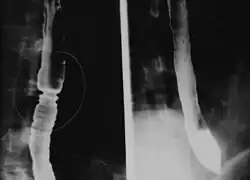

Estrechamiento del esófago que suele producir impactación alimentaria, disfagia y reflujo. Los niños pequeños con esofagitis eosinofílica pueden tener dificultad para comer, dolor abdominal o vómito. Es más común en hombres, y afecta tanto a adultos como a niños.[1]

La esofagitis eosinofílica se caracteriza por infiltración densa de eosinófilos en el epitelio escamoso del esófago. Se piensa que podría tratarse de una reacción alérgica a un alimento consumido, tomando en cuenta el importante papel que desempeña el esófago en las reacciones alérgicas. Los eosinófilos son células inflamatorias que producen una variedad de citocinas, las cuales inflaman el tejido esofágico circundante. Esto resulta en dolor y enrojecimiento visible durante una endoscopía.[1]